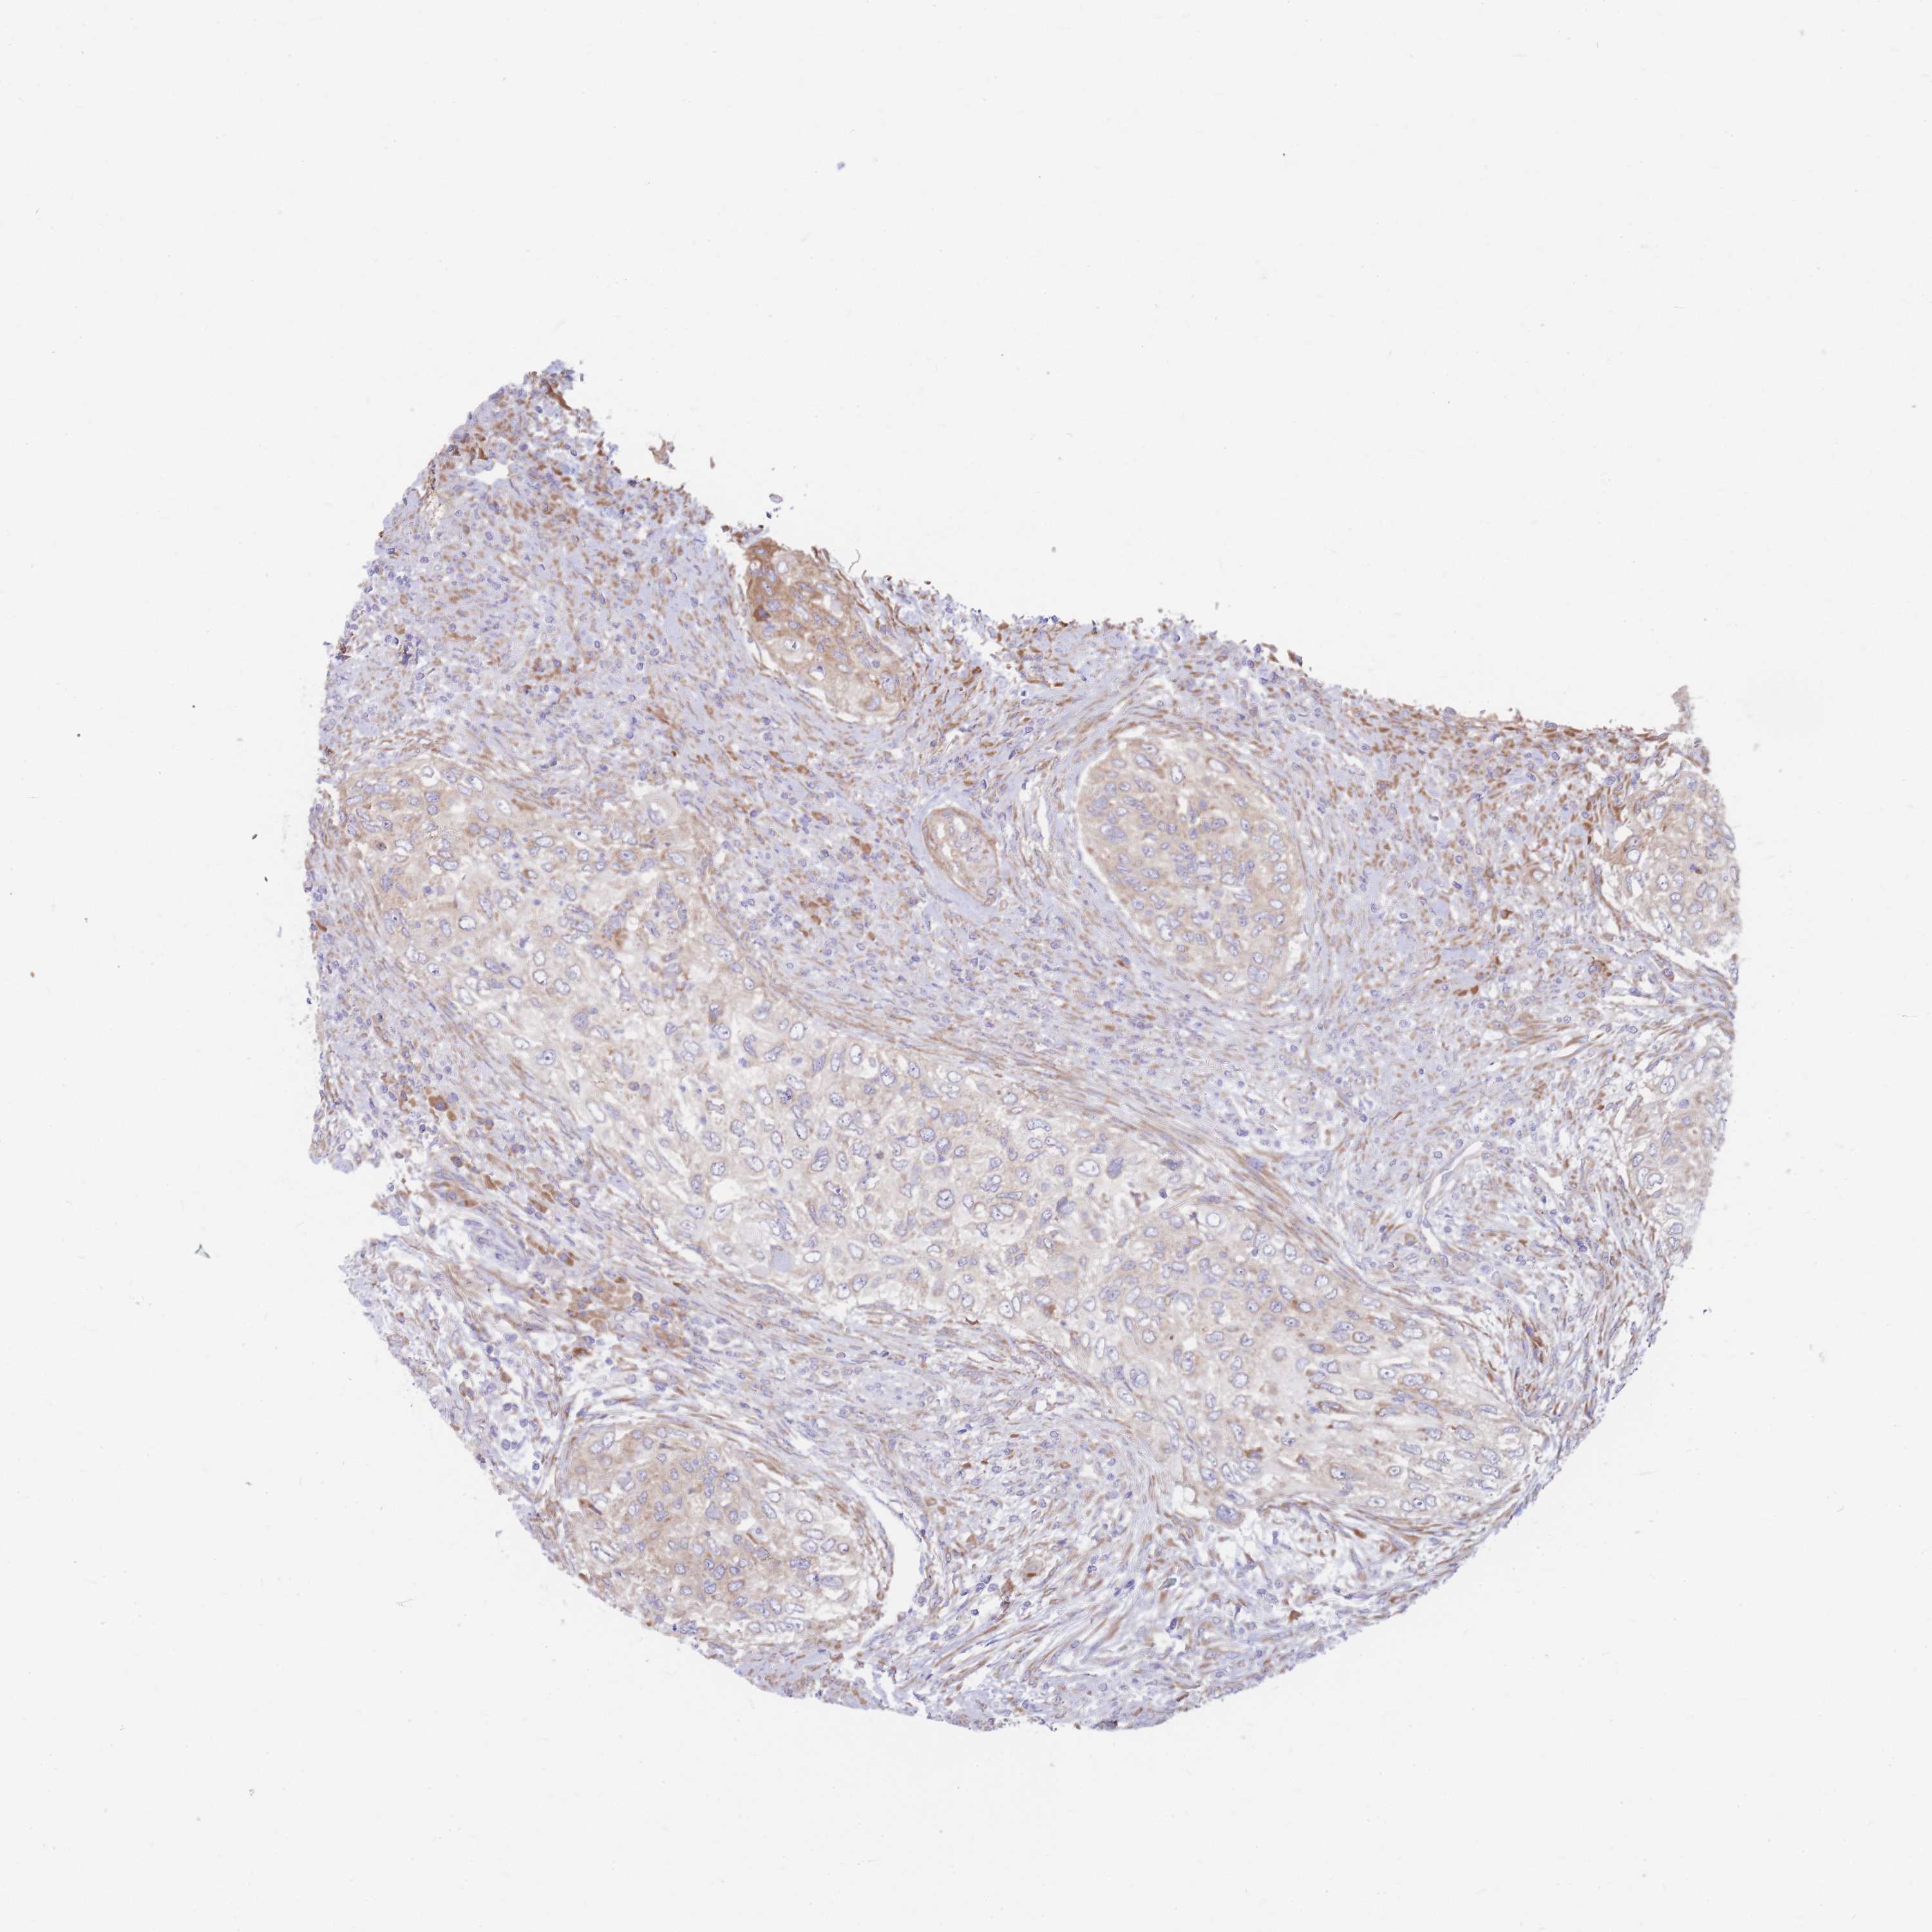

UROTHELIAL CANCER - Protein expressioni

A mouse-over function shows sample information and annotation data. Click on an image to view it in a full screen mode. Samples can be filtered based on level of antibody staining by selecting one or several of the following categories: high, medium, low and not detected. The assay and annotation is described here.

Note that samples used for immunohistochemistry by the Human Protein Atlas do not correspond to samples in the TCGA dataset.

Antibody stainingi

Antibody staining in the annotated cell types in the current human tissue is reported as not detected, low, medium, or high, based on conventional immunohistochemistry profiling in selected tissues. This score is based on the combination of the staining intensity and fraction of stained cells.

Each image is clickable and will lead to virtual microscopy that enables deeper exploration of all samples and also displays staining intensity scores, fraction scores and subcellular localization as well as patient and tissue information for each sample.

Antibody HPA045095

Antibody HPA050165

Urothelial carcinoma, Low grade

Urothelial carcinoma, High grade

Urothelial carcinoma, NOS